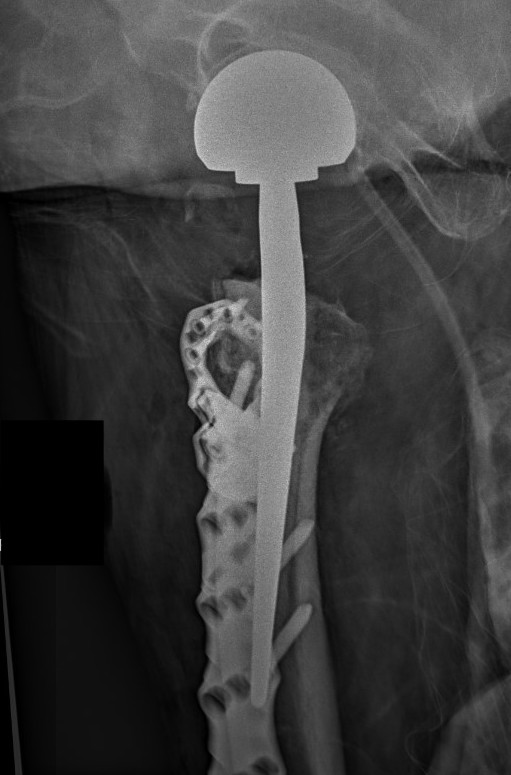

B. Cephalomedullary nails

- gold standard

Piriformis reconstruction Gamma nail TFNA with helical screw Intertan nail

B. Exchange nailing

C. Hemiarthroplasty / THA